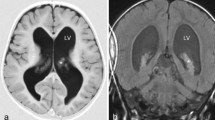

A 1-year-old patient, product of preterm gestation because of premature rupture of membranes, and previously healthy, presents with vomiting and irritability. Communicating hydrocephalus is evident in computed tomography (CT); VPS is placed, and 45 days after surgery, the patient developed ascites. CT abdomen shows free fluid in the cavity, without a solid or hollow viscera lesion. VPS is externalized, reporting drainage volumes of 1000–1200 ml/day of CSF, without signs of infection. Given such high output, magnetic resonance imaging (MRI) is performed showing bilateral CP hyperplasia (Figs. 1 and 2). The bilateral endoscopic procedure is performed in 2 stages: first, only CP cauterization (CPC). Subsequently, CSF flow decreases by 800 ml/day, and bilateral plexectomy was performed using a right frontal approach and performing a posterior septostomy, decreasing CSF outflow to 120 ml/day. It is decided to install VPS. A biopsy confirmed the diagnosis of CP hyperplasia.

There are several types of hydrocephalus, and its differential diagnosis is a major concern, such as what happens in CP hyperplasia and CPP diagnosis. This kind of hydrocephalus commonly leads to high rate of CSF production. The best mechanism of diagnoses is the MRI; the ideal treatment according to our experience corresponds to total plexectomy followed by total CPC. Despite the current knowledge about hydrocephalus, we remain without a complete understanding of the pathophysiology of this condition. GS could be more important than conventional concept of reabsorption of CSF in the arachnoid villi; therefore, GS could be a new key point, which will guide future investigations. The new concepts of AQPs 1 and 4 are involved in the physiology of the CSF production and open the possibilities of new pharmacological approaches. It is even possible that disorders in AQP1 on endothelial cells in specialized circumventricular organs like subcommisural structure might be associated with congenital hydrocephalus. There are few cases like ours written in the literature; we believe this kind of example switches on the alarms and should be taken into account always in the mind of the neurosurgeons. Further studies are required to corroborate these premises and elucidate the pathophysiological mechanisms underlying CSF circulation diseases.